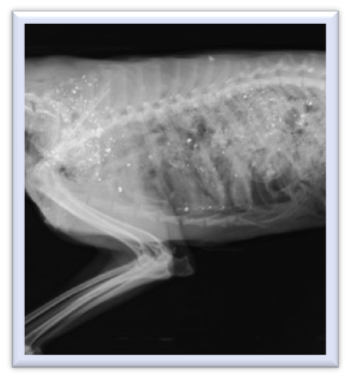

Volunteers quickly began supportive care and chelation therapy (described below) and scheduled radiographs. The x-ray images did not show evidence of the bright metallic opacity that would indicate lead, either from a bullet wound or ingestion of prey containing lead. Doctors suspected the bird had ingested prey containing lead and had already passed the prey through its digestive system, but the lead had been absorbed and was exerting the physiologic effects. Over the course of several days, the bird’s mentation and posture dramatically improved. It began standing upright, fighting handlers, and swallowing food on its own. Subsequent blood lead levels began decreasing. Sadly, the patient succumbed to other injuries sustained while it was debilitated from the lead’s effects. This toxicosis resulted in the bird stranded on the ground before being brought to the clinic.

Within days, a second eagle presented to the wildlife clinic. Similarly, the patient exhibited neurologic signs without evidence of trauma and the team ran a blood sample through the lead analyzer. This time, the level was read as 14.7ug/dL – while still an elevated level, it indicated a better prognosis for the bird. As with the first bird, this eagle did not have radiographic evidence lead in its system. Unfortunately, the eagle died within 24 hours of intake. A necropsy (autopsy) performed revealed evidence of both a viral disease process and head trauma.

A third eagle, presenting within two weeks of the first eagle, exhibited comparable clinical signs. Again, its blood lead levels were too high for the analyzer to read, and at the time that the radiographs were taken there was no evidence of lead. Despite chelation therapy, this eagle was found deceased in its cage before further lead readings could be evaluated.

Diagnosis of lead toxicosis is usually done through bloodwork and radiology. Because our clinic has an in-house lead analyzer, teams are able to determine lead levels quickly – although the decision to do so is based on suspicion. In the above cases, teams did not have access to the radiology department during off-hours, so began treatment prophylactically and took radiographs at the next available time. As is common with lead ingestion, none of the patients had evidence of metallic sources in their bodies.